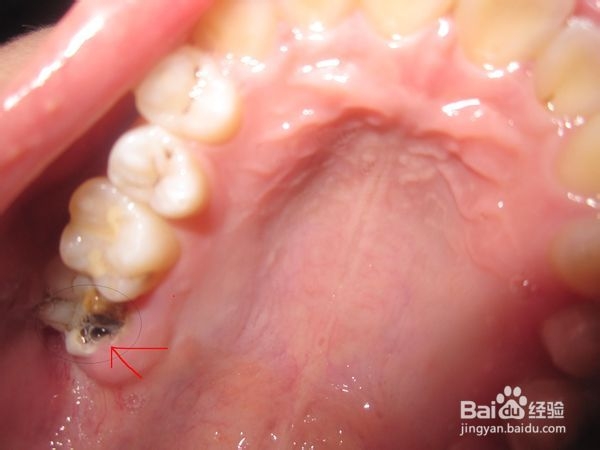

3、 智齿冠周炎:智齿是牙列中最后萌出的牙,多于18~25岁萌出,因萌出位置不足,可导致智齿萌出不全而异位或阻生,牙冠部分外露于牙龈之外,部分被牙龈覆盖。牙龈与牙体之间形成一个狭窄较深的盲袋,容易积存食物碎屑和细菌,一般刷牙漱口难以清洗干净;加之冠部牙龈易因咀嚼食物而损伤,形成溃疡。当全身抵抗力下降、细菌毒力增强时,便可引起牙冠周围牙龈组织炎症肿胀。